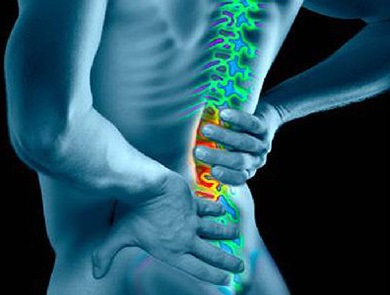

- Simptomele de osteoartrita a coloanei vertebrale

osteoartrita a coloanei vertebrale

Cu acest tip de tablou clinic este după cum urmează:

- Afectate cartilaj intervertebral.

- După ce procesul a implicat corp vertebrale, mușchii și ligamentele.

- Apar dureri severe pot limita mobilitatea.

Cel mai adesea boala este expusă lombară și cervicală.

Deci, uita-te leziuni distrofice ale vertebrelor

Osteoartrita a coloanei vertebrale este un legate de varsta, boli, așa cum se întâmplă de multe ori ca urmare a uzurii cartilajului. Patologie se dezvolta pe parcursul mai multor decenii si poate fi simtit doar simptome minore.

La vârf de boala format osteofite, care vatămă suprafață și dau naștere la dureri severe. După aceea, inflamatia afecteaza muschii si ligamentele, reducând în același timp tonul lor. deformare spinarii devine vizibil cu ochiul liber.

Simptomele de osteoartrita a coloanei vertebrale

Principalele caracteristici includ:

- Durerile de spate după exercițiu. senzații dureroase sunt mai aproape de dimineața după vacanță.

- Apariția durerii constante plictisitoare timp de noapte. Acest lucru se datorează stagnarea sângelui în vasele de sânge care hrănesc coloanei vertebrale.

- Limitarea mobilității coloanei vertebrale și a gâtului.

- deformare spinarii, o schimbare în postură.

- Creșterea în loc de vertebre deteriorate.

- Criza de timp în timp ce efectuează diferite acțiuni.

Durere în leziuni ale coloanei pot fi de diferite tipuri. Ele pot fi lung sau pe termen scurt, dar manifestă acut, apar după activitatea de repaus sau de muncă.

Important! În cazul în care sunt în curs de desfășurare de durere, vorbim despre spasme musculare și nervi ciupite.

Adesea, există durere la nivelul coloanei vertebrale inferioare